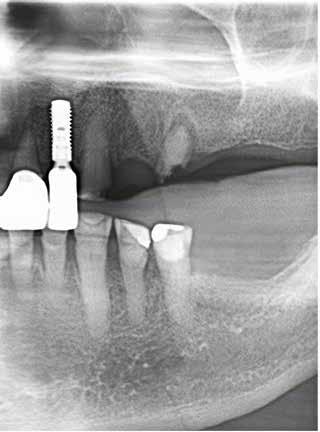

REZAI E, PERSSON M, NØRHOLT SE Statisk computerassisteret implantatkirurgi / 578

I den tredje artikel, som er en oversigtsartikel, vender vi os mod computerassisteret implantatkirurgi. Vi har igennem de senere år løbende bragt artikler om mange forskellige aspekter af implantatkirurgi. Denne artikels fokus er statisk computerassisteret implantatkirurgi, der indebærer anvendelse af en guideskinne, der støtter borets retning og dybde, således at den virtuelt planlagte implantatposition overføres til patienten. Metoden er anvendelig, hvor implantater indsættes tæt på vigtige anatomiske strukturer eller i den æstetiske zone. Artiklen diskuterer fordele og begrænsninger ved

anvendelse af metoden sammenlignet med eksempelvis frihåndsimplantatkirurgi.